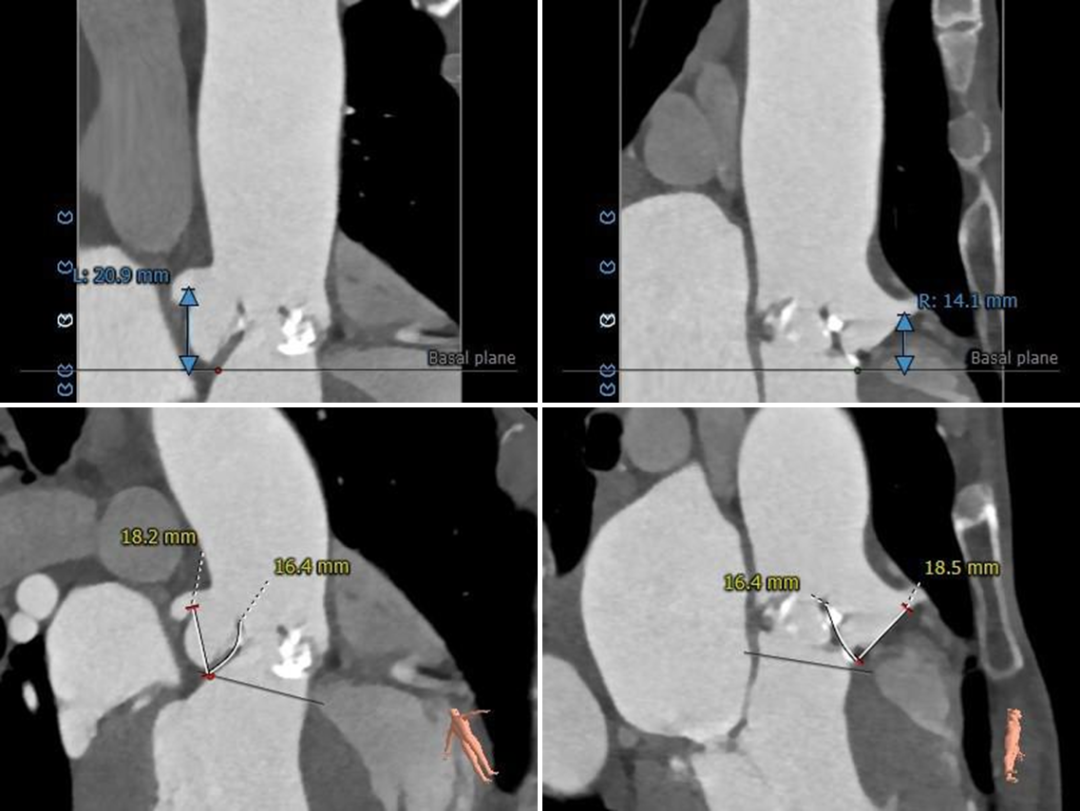

根部测量

瓣环平均径22.2mm,瓦氏窦、STJ、升主内径略小,非横位心

冠脉测量

冠脉开口高度可,切线角度测量,

左窦瓣叶长于LCA开口到瓣叶根部距离

连续时相观察左窦瓣叶动度灵活,

收缩期瓣叶接近左冠开口高度;

3D打印模型22mm球囊扩张测试,左窦冗余空间小

钙化分布

钙化主要分布于R-N之间,HU850 343mm³